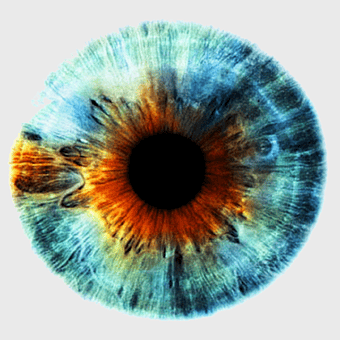

Human eye closeup, iris and sclera details, ophthalmology stock image, eye organ anatomy, ocular health, visual system study, eye texture analysis -

Human eye cornea, visual perception closeup, eye examination details, iris color analysis, ocular health, eye anatomy illustration, corneal structure view -

blue iris closeup, human eye pigment, visual perception organ, eye color analysis, ocular anatomy details, iris texture patterns, eye health examination -